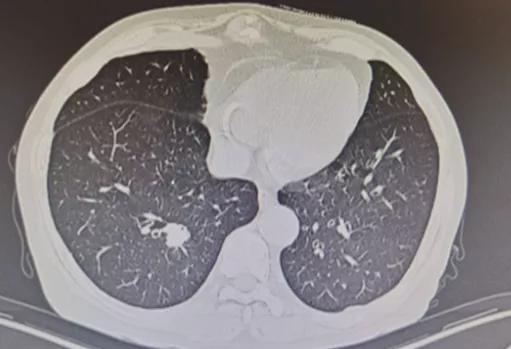

非手术活检的局限性

但是非手术活检获取的标本都是小标本,所以取标本有限。如果病理报告基于针尖大小的组织样本,那就存在许多不确定性。上图所示,是我们的一个病例,4月21日,外院CT引导下经皮肺穿刺,我院病理会诊为慢性炎症;5月16日入院,我建议再做一次活检,于是5月19日经皮肺穿刺,病理提示还是慢性炎症;两次病理提示均为慢性炎症,但是完全用慢性炎症解释这个肺结节还有些疑问,我建议再做一次经皮肺穿刺,6月7日第三次活检的病理结果提示为中分化腺癌,而且基因检测提示ALK阳性,是黄金突变,靶向治疗效果很好。因此,我们取小标本的时候,要慎重解释阴性结果。